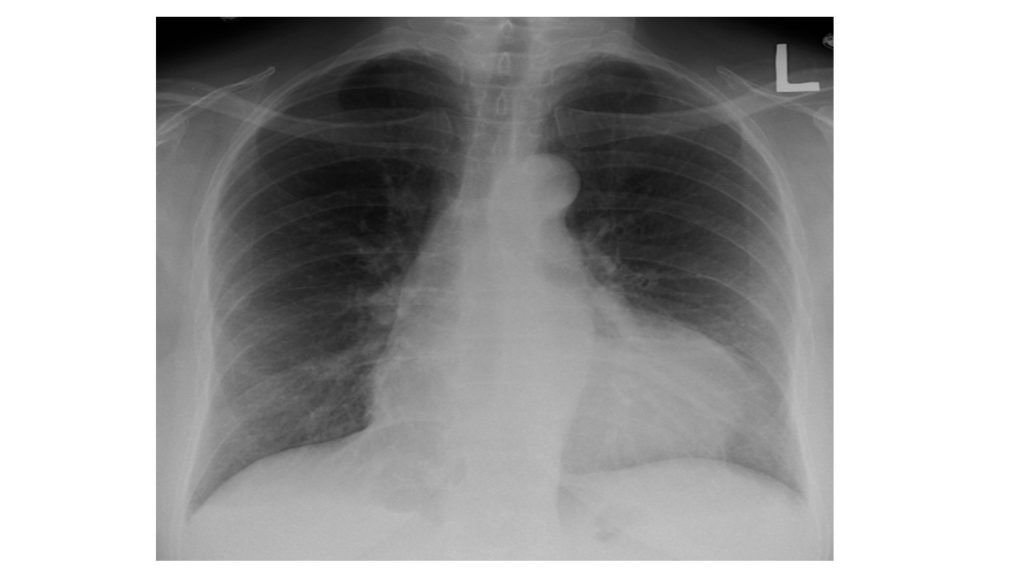

- Es conveniente realizar pruebas por imagen para poder observar el estado del corazón, los pulmones, las articulaciones o los músculos. Estas pruebas a las que nos referimos pueden ser una radiografía (RX), una Resonancia Magnética (RMN) o bien una ecografía.